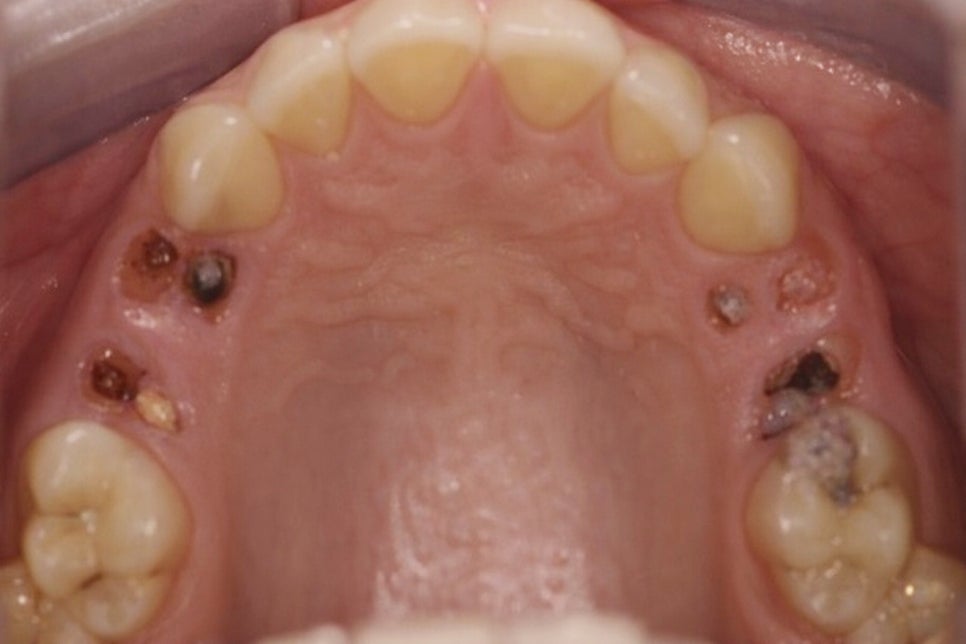

대표적으로는 치주질환, 심한 충치,

외상 등이 주요 원인으로 꼽힙니다.

🔻 먼저 치주질환은 잇몸과 치아 주변 조직에

염증이 발생하면서 점차 치조골이 흡수되고

치아를 지지하고 있던 구조가 약해지면서

이가 흔들리거나 결국 발치가 필요한

상태에 이를 수 있습니다.

이는 특히 초기에 증상이 뚜렷하지 않아

방치되는 경우가 많기 때문에

정기 검진이 더욱 중요해집니다.

🔻 심하게 진행된 충치 역시 주요 원인으로

법랑질과 상아질을 지나 내부까지 깊게 진행되면

파절로도 이어질 수 있습니다.

이러한 경우 신경치료나 보철 수복이 어렵다면

발치를 고려해야 될 수도 있으며